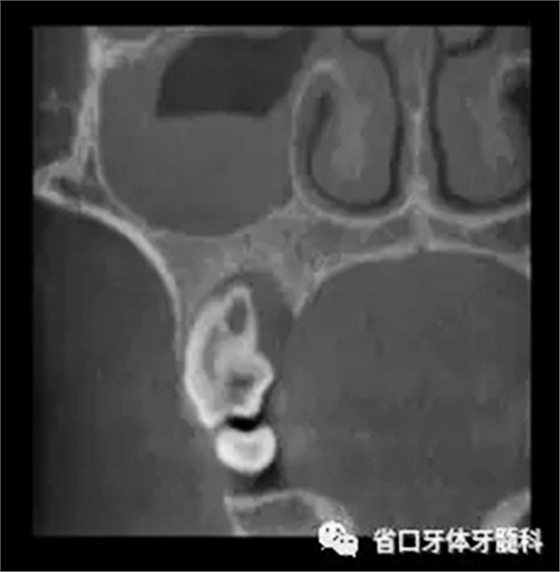

圖3 CBCT(2016-11-13):15由髓腔至根管內(nèi)見團(tuán)塊阻射影像,阻射影中央為透射影,根尖1/3處見根管膨大,腭側(cè)牙槽骨破壞,根尖周低密度影范圍大,上頜竇黏膜增厚。